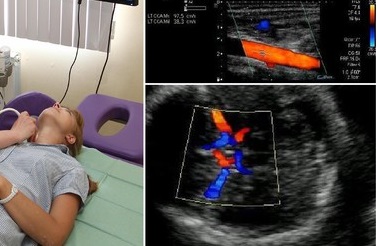

- Extracranialis. Ez Doppler vizsgálatok hajók a nyak, arc, stb más szóval - ezek a hajók, amelyek részt vesznek a vérellátás a fej és a nyak, de ki a koponyaüreget.

Színes kétoldalas mapping - az ilyen típusú diagnózis, amely egyesíti a hagyományos és a Doppler ultrahang. DRC - egy modern típusú diagnózis, ami nem károsabb, de ez drágább, mint a hagyományos Doppler. A módszer előnyei az a képesség, hogy vizsgálja nemcsak a vér áramlását, hanem a hajó. Most már egyre gyakrabban az első módszer a DRC nem Doppler. Ahhoz azonban, hogy eldönteni, mi a legjobb, hogy végre kell orvoshoz fordulni.

Hogy van a Doppler ultrahang

Végezze el a Doppler ultrahang a nyak hajók és agyi erek lehetnek a különböző magán- és az állami kórházak. Közülük azok, amelyek szakosodott kizárólag a neurológia és diagnosztikai központok. Érrendszeri Doppler végezhet szabad közkórház, feltéve, hogy az irányt a neurológus.